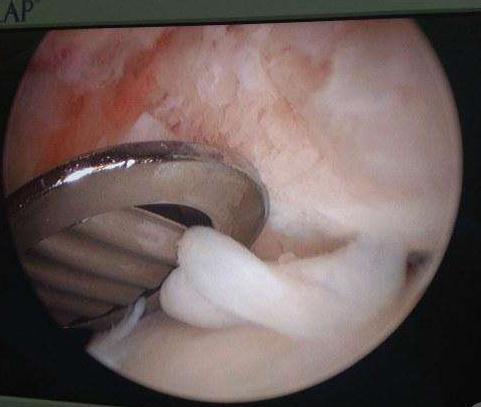

骨刺是怎么长出来的呢?很多人一听到骨刺,就从字面理解,认为是从骨头上长出刺,刺会扎进肉里,从而导致肿痛,实际上当然不是这么回事。在正常的关节中,骨端会有一层光滑的、薄薄的釉白色软骨,咱们在啃猪骨头的时候一定见到过。关节软骨在关节中起着缓冲作用,但会因为过度使用、不正确使用遭到磨损、破坏,失去软骨保护的软骨下骨端相互摩擦,就会造成骨质增生,骨赘形成,也就是骨刺!

破损的软骨碎屑会游离在关节腔中,增生的骨刺会压迫周围组织,关节就会出现肿、热、痛等炎症反应,这就导致了骨关节炎的发生。

当通过非药物治疗和药物治疗等保守治疗,患者的病情仍然没有得到改善时,患者就要考虑是否进行手术治疗,骨关节炎常见的手术治疗包括针刀镜维持手术、截骨术,以及关节置换术。